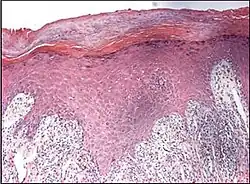

Psoriaform dermatitis typically displays:[2]

- Regular epidermal hyperplasia, elongation of the rete ridges, hyperkeratosis, and parakeratosis.

- Usually:A superficial perivascular inflammatory infiltrate

- Often: Thinning of epidermal cells overlying the tips of dermal papillae (suprapapillary plates), and dilated, tortuous blood vessels within these papillae

| Psoriasis | Present | Diffuse | Regular | Thin | Decreased or absent | Increased mitoses; minimal spongiosis Clubbed rete pegs[12][13] | Absent |